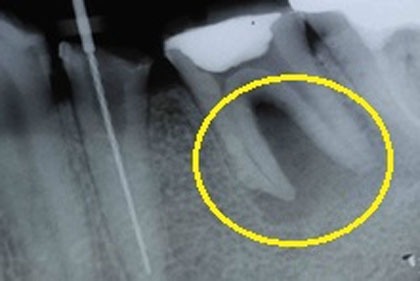

黄色枠内の色の濃い部分は、

炎症で骨に大きな空洞ができています。 -

治療5年後、影もなくなり、

新しい骨ができてるのも確認できます。